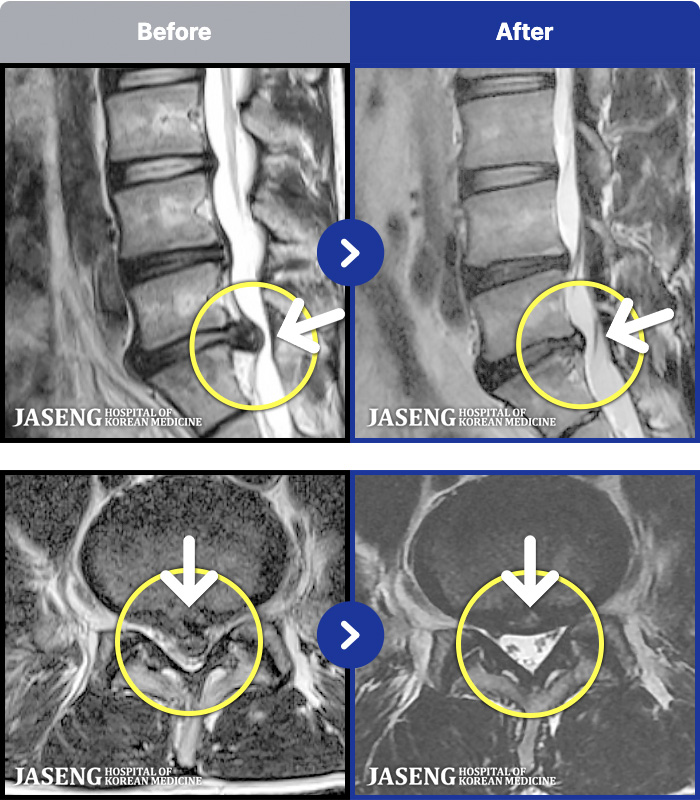

1,291 MRI ũ ʸ Ȯϼ.